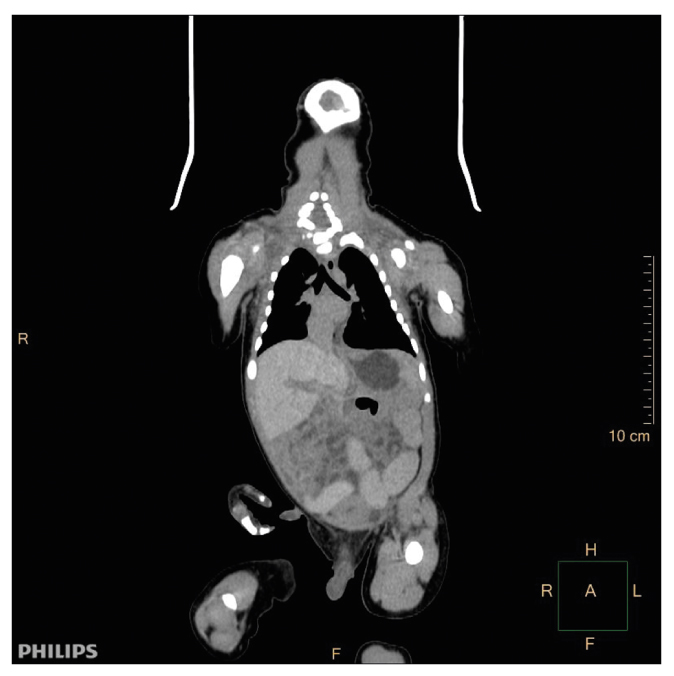

В декабре 2019 г. в помещении мусоросортировочного цеха Раменского района Московской области на сортировочной ленте обнаружен труп новорожденного ребенка мужского пола с фрагментом пуповины. Труп представлен двумя фрагментами: первая часть — головой, шеей, правой и левой верхней конечностью, грудной клеткой и верхней третью живота; вторая часть — тазом и нижними конечностями. Первая и вторая части трупа соединяются тканевой перемычкой (кожей с мягкими тканями) передней брюшной стенки (рис. 7).

Рис. 7. Труп ребенка, внешний вид: а — при обнаружении; b — КТ, 3D-изображение.

Fig. 7. Appearance of the corpse of the child: а — upon detection; b — 3D image.

При КТ основными находками были костные повреждения: множественные повреждения и переломы костей черепа (рис. 8, 9) — лобной кости, чешуи слева, глазничной и носовой части лобной кости слева, обеих теменных костей, затылочной кости (базилярной, латеральной частей и чешуи) со смещением, захождением и деформацией костных отломков, височных костей, тела и больших крыльев основной кости; расхождение швов мозгового и лицевого черепа с деформацией черепной коробки в виде уплощения с боков; перелом скулоорбитального комплекса справа; позвоночного столба (латеральное смещение С1-позвонка вправо, С7-позвонка влево); полная сепарация позвоночного столба с большим диастазом на уровне середины тела Th11-позвонка, с переломом тела позвонка; множественные переломы большинства ребер; полная сепарация всех ребер слева на уровне реберно-позвоночных сочленений, с диастазом; деформация грудинного конца ключицы справа; переломы крыла подвздошной кости справа, седалищной кости справа; неполный перелом средней трети диафиза правой бедренной кости, средней трети диафиза правой большеберцовой кости. Вещество головного мозга было в состоянии декомпозиции (см. рис. 8), представлено мягкотканным субстратом с наличием газа и плотных включений; воздухоносные пространства пирамид височных костей выполнены мягкотканным субстратом. Левое глазное яблоко деформировано, неправильной формы. Ушные раковины и наружный нос правильно сформированы, деформированы. Грудная клетка деформирована, гемитораксы асимметричны. Средостение представлено в виде отдельных мягкотканных элементов с наличием плотных включений. Сердце в размерах не увеличено, располагается вне грудной полости. Легочная ткань: легкие располагаются вне грудной полости, повышенной плотности (тотально уплотнены), не расправлены (рис. 10). В структуре легочной ткани прослеживаются элементы газа, отдельные — в виде трубчатых структур — вероятно, отображение бронхов. В толще легочной ткани и вокруг видны структуры высокой плотности — вероятно, инородные тела в сочетании с костными фрагментами. Визуализируются трахея и проксимальные отделы правого и левого главных бронхов; дистальнее просвет бронхов обрывается. Нарушение целостности брюшной стенки с полной эвентрацией органов. Полые и паренхиматозные органы представлены мягкотканными структурами без органной дифференциации, смешанными с инородными телами, чередующимися с множественными пузырьками газа. Газ определялся в мягких тканях, в том числе мошонке, грудной клетке, малом тазу, полости черепа, позвоночном канале.

Рис. 10. КТ: легкие располагаются вне грудной полости, тотально уплотнены, не расправлены.

Fig. 10. Computed tomography findings: the lungs are located outside the chest cavity, totally compacted, not straightened.

На основании полученных данных сделан вывод: новорожденный является зрелым, доношенным, продолжительностью внутриутробной жизни около 36 нед. Ребенок родился мертвым, о чем свидетельствуют данные предсекционного КТ (тотальное уплотнение обоих легких — нерасправленные легкие) и судебно-гистологического исследования. Повреждения при разделении туловища младенца образовались посмертно, скопления газа — в результате гнилостных изменений.